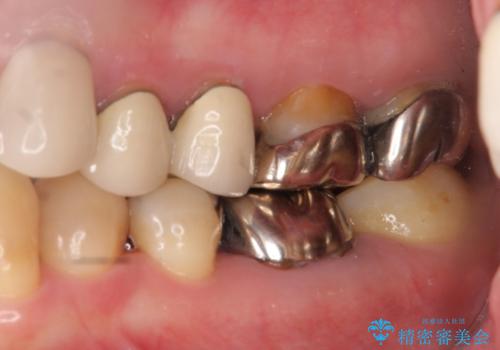

銀歯も白くということでしたので虫歯治療も一緒に行っています。

左上7の根の治療や左下56銀歯の治療なども行いました。

右下7は根管治療をおすすめしましたが、患者様のご希望により抜歯となり、そのスペースを利用して下の前歯をならべています。